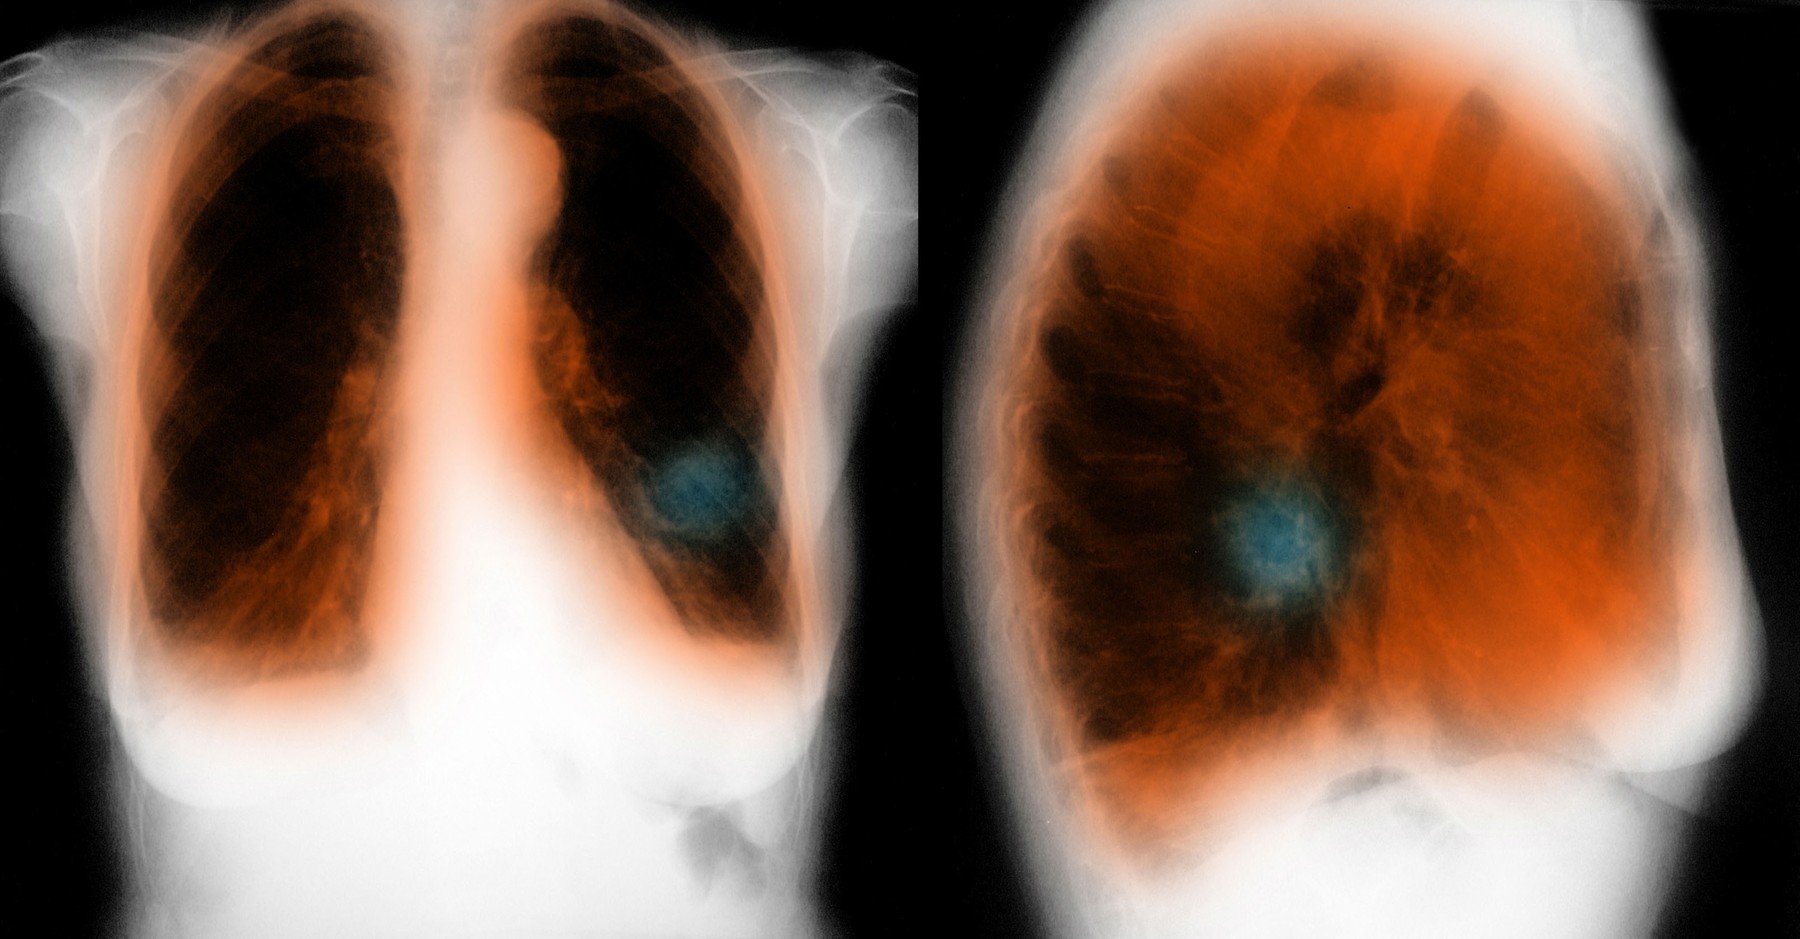

Kronična obstruktivna pljučna bolezen (KOPB) je težko kronično pljučno obolenje, pri katerem je normalen pretok zraka v pljuča zmanjšan, kar otežuje dihanje. Med ljudmi je znana tudi kot bolezen težke sape, pogosto s pridruženim kašljanjem. Sčasoma lahko se lahko zaradi bolezni razvije tudi okvara pljučnih mešičkov, ki propadajo in vodijo v prenapihnjenost pljuč.